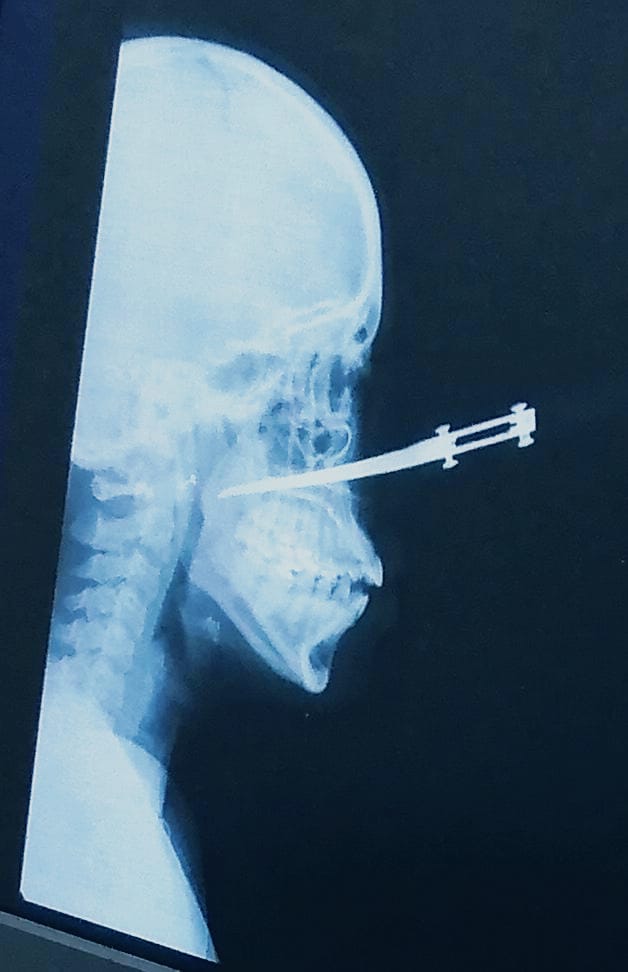

Mujer atacada en el rostro

La mujer se salvó de morir y fue intervenida quirúrgicamente. Las autoridades están tras el paradero de los responsables del hecho.

Por fortuna Yoleydis Montaban Hernández, de 35 años, está viva para contar los hechos que hoy la tienen recluida en un centro asistencial de Cartagena con un cuchillo incrustado en su rostro, que le dejaron delincuentes que intentaron robarla en el barrio El Pozón, momentos en que se dirigía a su lugar de trabajo.

Dijo que, “la primera reacción de uno es defenderse, inmediatamente me mandaron a mi un machetazo, mi hija metió la mano para evitar que me dieran y le dieron a ella fue en la mano, le cortaron dos dedos, afortunadamente no se lo rebanaron si no que fueron cortadas. Luego el otro el que tenía el cuchillito se le abalanzó fue a ella y le enterró el cuchillo en la cara”.

“No había ni a quien pedirle auxilio porque las calles estaban solas, mi hija afortunadamente podía caminar y llegamos al Hospital que nos quedaba a dos cuadras y allí el personal médico dijeron que el caso no era ahí, llamaron una ambulancia y nos llevaron al lugar donde la atendieron. Tiene otra herida en el cachete del mismo lado donde le incrustaron el cuchillo”, sostuvo Humberto Montalban.

La joven fue intervenida quirúrgicamente, los galanos señalaron que esperarán su recuperación a ver si es necesario que un cirujano plástico le reconstruya su rostro.

Por la nariz le entró el cuchillo, eso era muy delgadito, afortunadamente no le llegó a la columna, el cuchillo le llegó hasta un poquito más allá de la garganta, pero por fortuna no le dañó ningún órgano. Me siento impotente, sentí ganas de correr tras ellos para que me mataran, pero era más importante atender a mi hija. Ellos salieron caminando rápido, inmediato salieron de la otra cuadra se perdieron, no nos quitaron nada de valor”, argumentó Humberto.